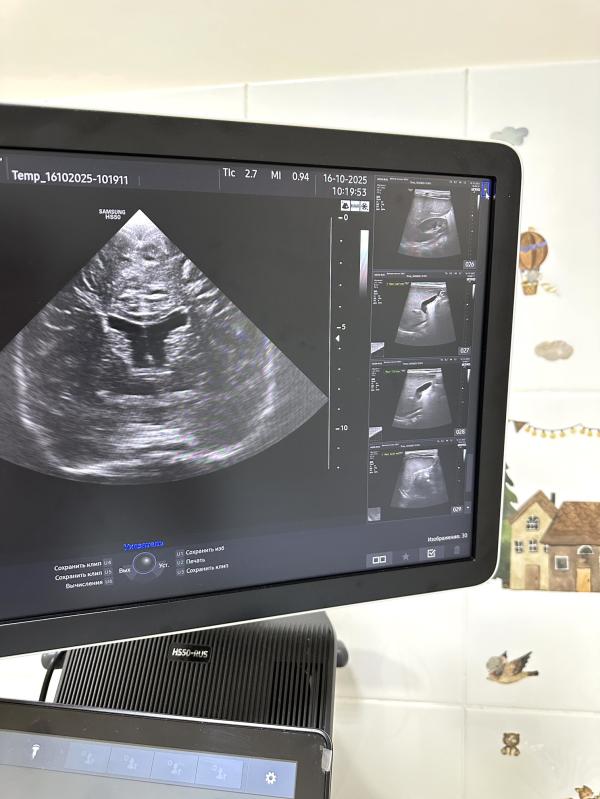

- Изображение выводится на экран аппарата, позволяя нам рассмотреть внутренние структуры мозга.

*На узи-снимке головной мозг с признаками расширения боковых желудочков.